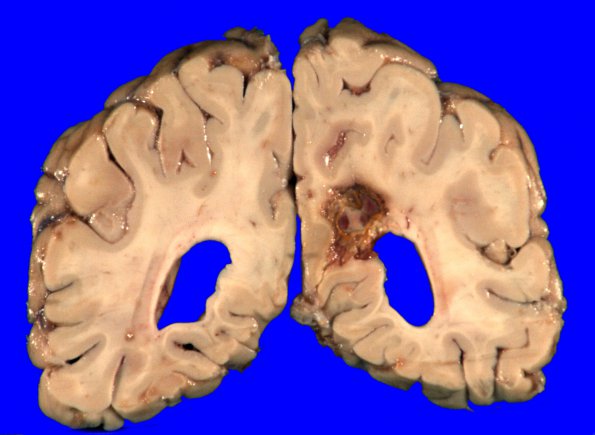

17A1 Infarct, subacute (Case 17) (hypertensive vessels) Gross _2

17A1,2 Two grossly visible hemorrhagic infarcts were identified.